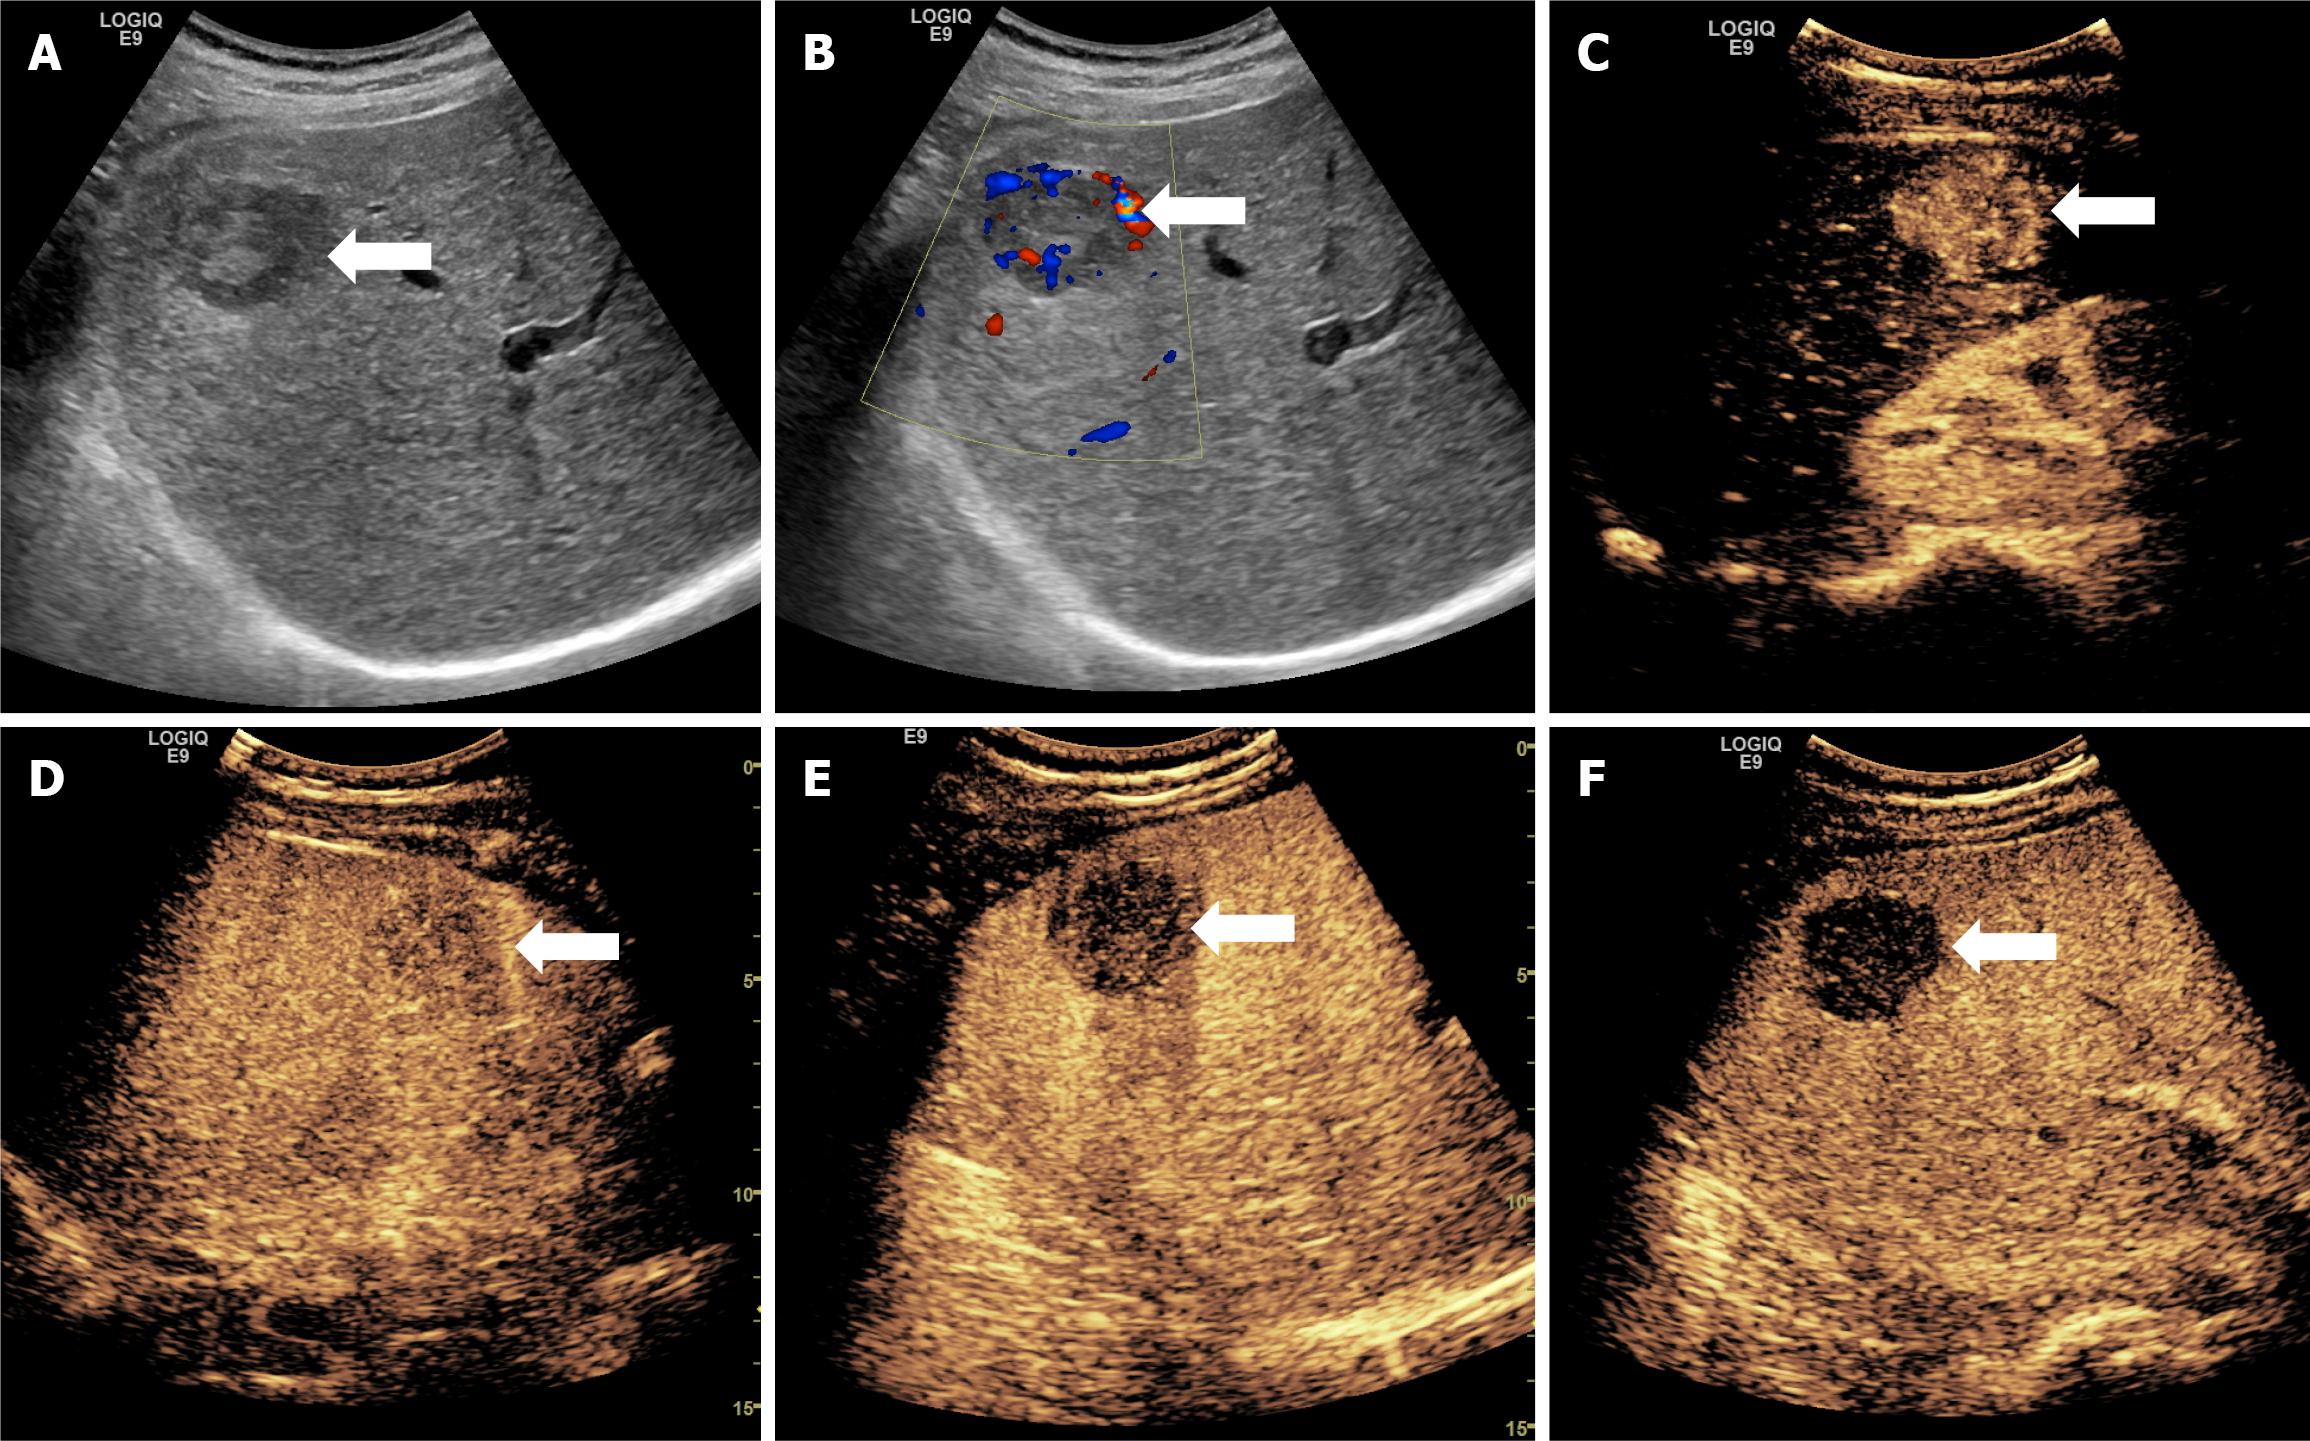

Figure 3 Ultrasound figures of a case of well-differentiated hepatocellular carcinoma.

The figure presents the case of a 54-year-old male patient with chronic hepatitis B, in whom a liver mass was revealed, well-differentiated hepatocellular carcinoma without vascular invasion, and a Ki-67 expression of about 50%. A: An ultrasound image showing a mass approximately 4.4 cm in diameter located in the right lobe of the liver; B: The ultrasound image showed abundant short linear blood flow signals in the lesion; C-F: Sonazoid-contrast-enhanced ultrasonography images showed a rapid enhancement of the mass in arterial phase and washout beginning in the late portal venous phase.